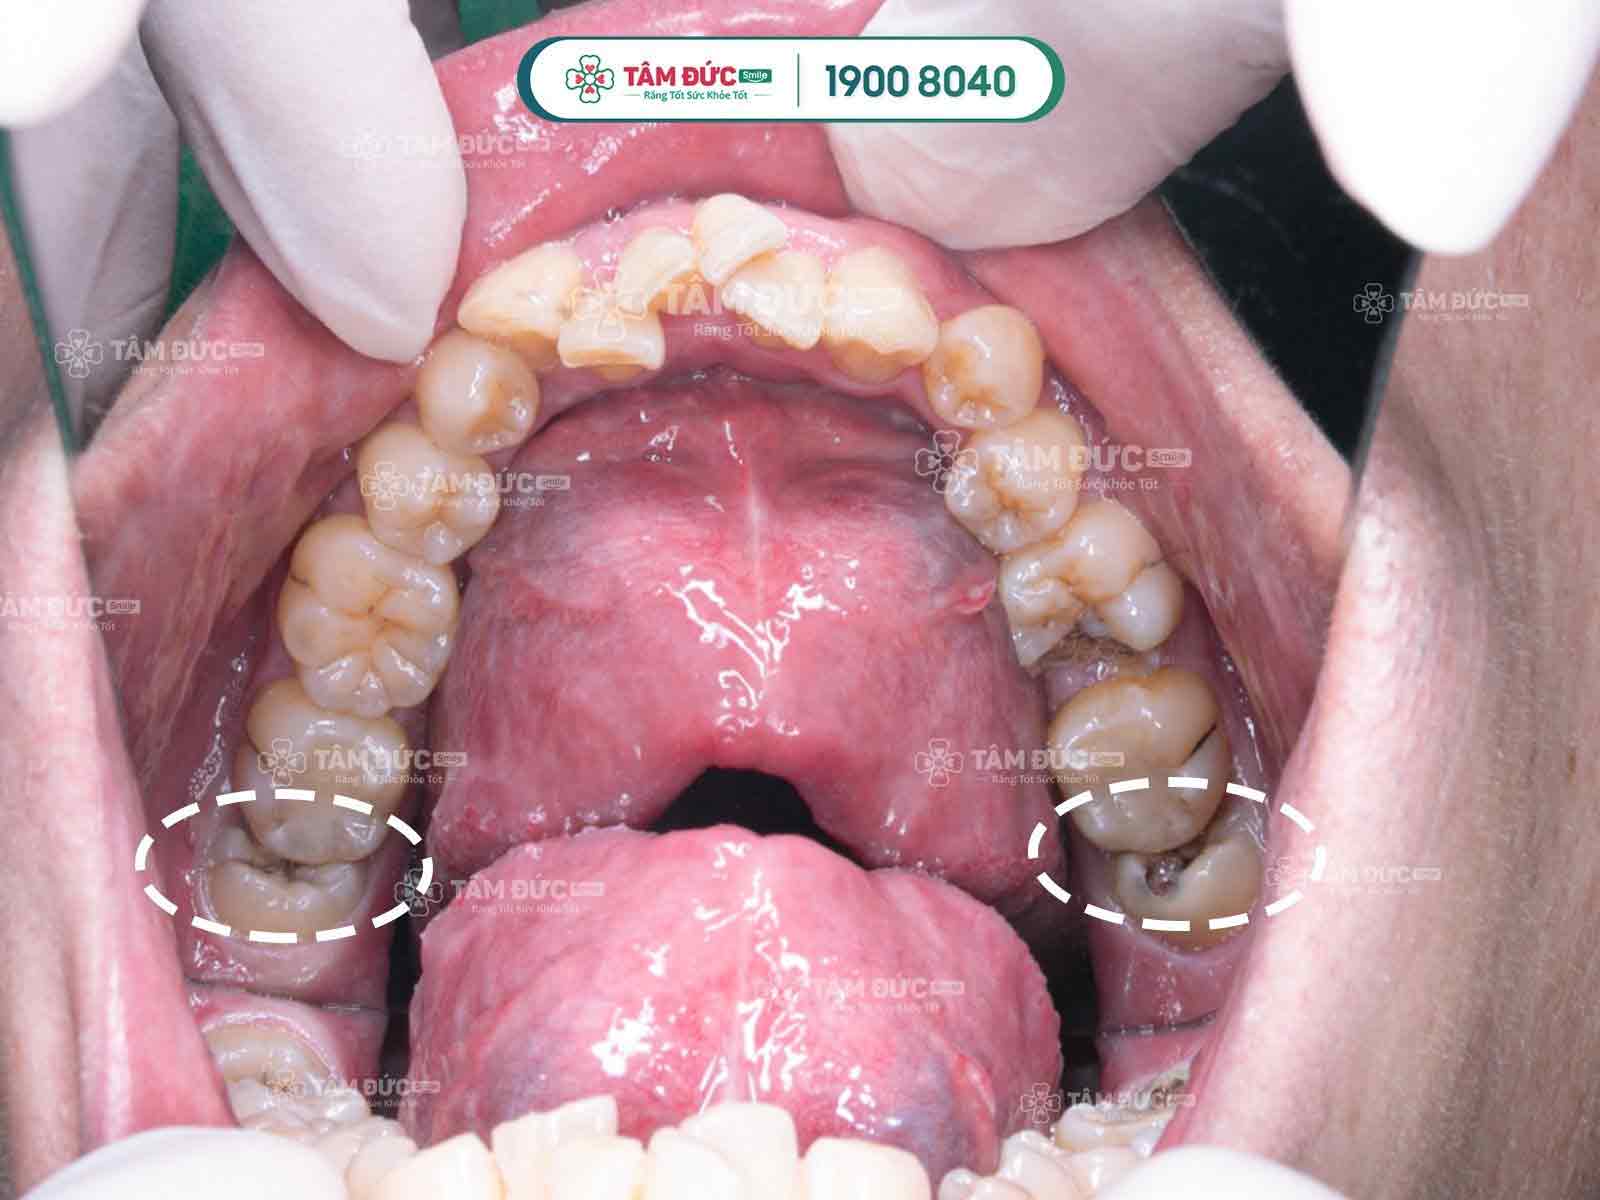

1.2.3. Sâu răng khôn

Vị trí răng khôn bị lệch là nơi rất khó vệ sinh, tạo điều kiện cho nhiều loại vi khuẩn có hại sinh sôi và phát triển, gây sâu răng, viêm nướu, viêm nha chu, tích tụ ổ mủ.

Răng khôn bị sâu cần được nhổ bỏ sớm